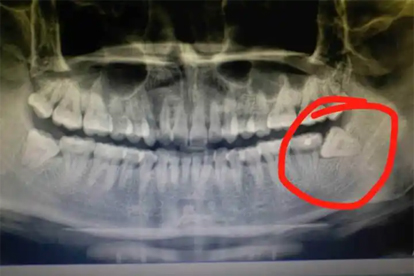

口腔科通过视诊可见智齿区牙龈瓣充血,X线片能明确智齿阻生情况。上火通常无特异性检查异常,中医舌诊可见舌红苔黄等实热证表现。

建议出现口腔不适时避免自行挤压肿胀部位,智齿发炎需尽早就医进行局部冲洗或拔除处理。日常保持口腔清洁,使用含氯己定的漱口水辅助消炎,饮食宜清淡并补充维生素B族。反复智齿冠周炎或持续发热者应拍摄口腔全景片评估手术指征。